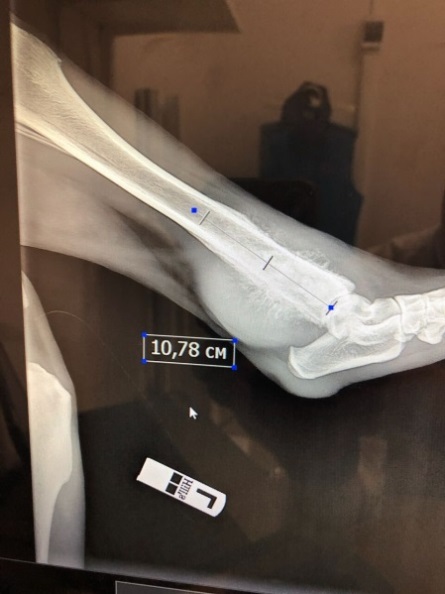

Рис. 1 — Рентгеновский снимок задней конечности животного до операции. Остеосаркомой поражено почти 11 см костной ткани.